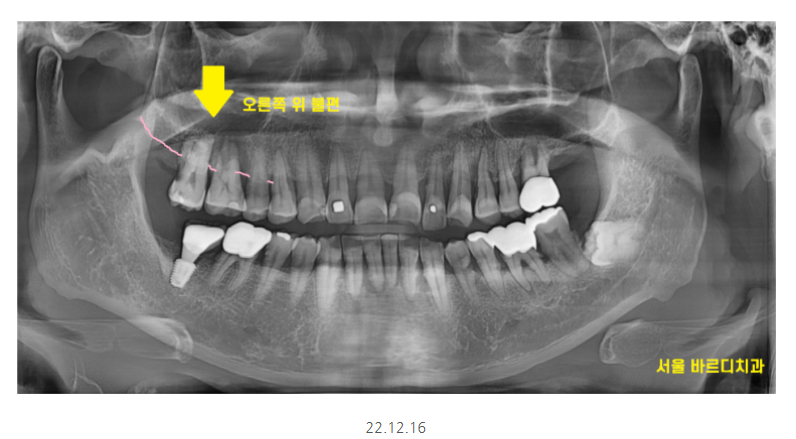

전반적으로 잇몸이 많이 내려가신 상황이었는데요.

불편을 호소하신 오른쪽 치아를 보니

잇몸뼈가 많이 내려가

치아를 움직여봤는데요.

어금니가 들썩 들썩

위 아래, 좌우로 움직였습니다.

x-ray상에서 치석이 보일정도로

치석도 많고 잇몸관리가 안되고 계셨어요.

오른쪽 어금니 시림으로 내원하셨지만

다른 치아들도 상태가 영 .. 좋지 않았죠.